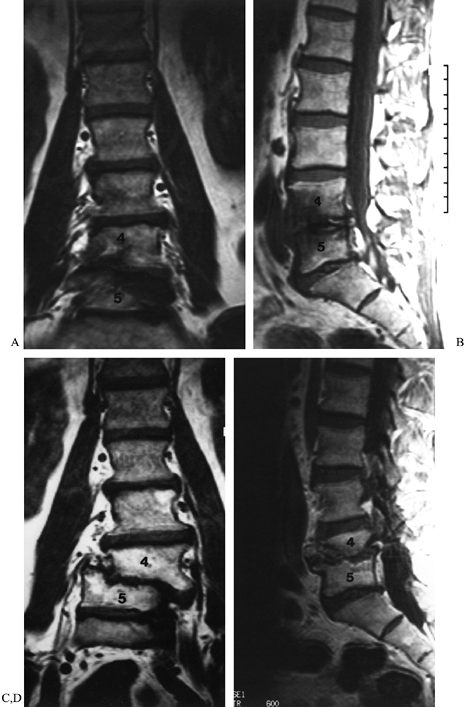

and parasagittal views of the thecal sac and foraminal narrowing, and

to identify disc degeneration, which may be helpful in planning for a

fusion. Its sensitivity in identifying other causes of back pain in

this population, including metastatic disease and occult infection, is

also an advantage. State-of-the-art technology in MRI has provided

sufficient bony detail to diagnose adequately facet overgrowth,

osteophyte formation, and other causes of LSS in most patients. This is

our routine test of choice (Fig. 149.5). In

some patients with previous surgery, however, it is helpful to use

postmyelographic CT scanning, which still provides better bony detail

and shows encroachment on the thecal sac and on the nerve roots in the

lateral recesses and foramina. Postmyelographic CT is not as specific

as MRI in identifying and differentiating postoperative scar tissue

from normal soft tissue, when differentiation is a consideration (5).

![]() |

Figure 149.5.

A 52-year-old man with recurrent back and right leg pain 8 years following a lumbar decompression and fusion from L4–S1. On T1-weighted axial MR images, right lateral recess stenosis at L2–L3 (arrows) is clearly demonstrated. Following repeat decompression and extension of his fusion to L-2 he had near-complete pain relief. |